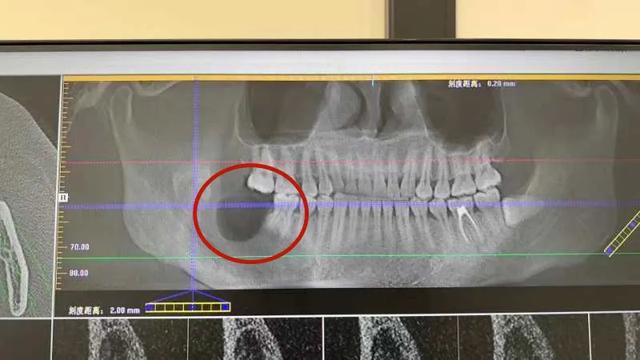

昆山市一医院口腔科立即安排

口腔颌面锥形束CT

结果提示

右下颌第一前磨牙远中至右侧下颌骨升支

见一大小约6.5cm*4.0cm 的椭圆形低密度影

囊腔压迫下牙槽神经管